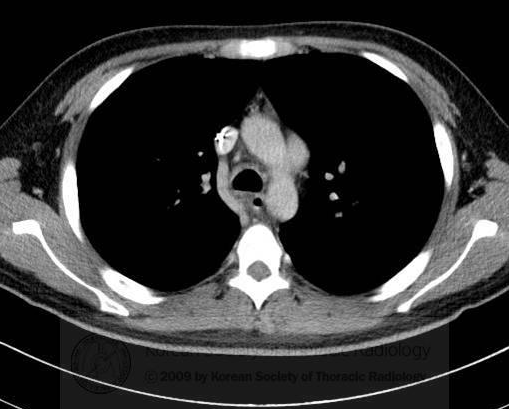

以影识病丨支气管壁增厚原因为何?